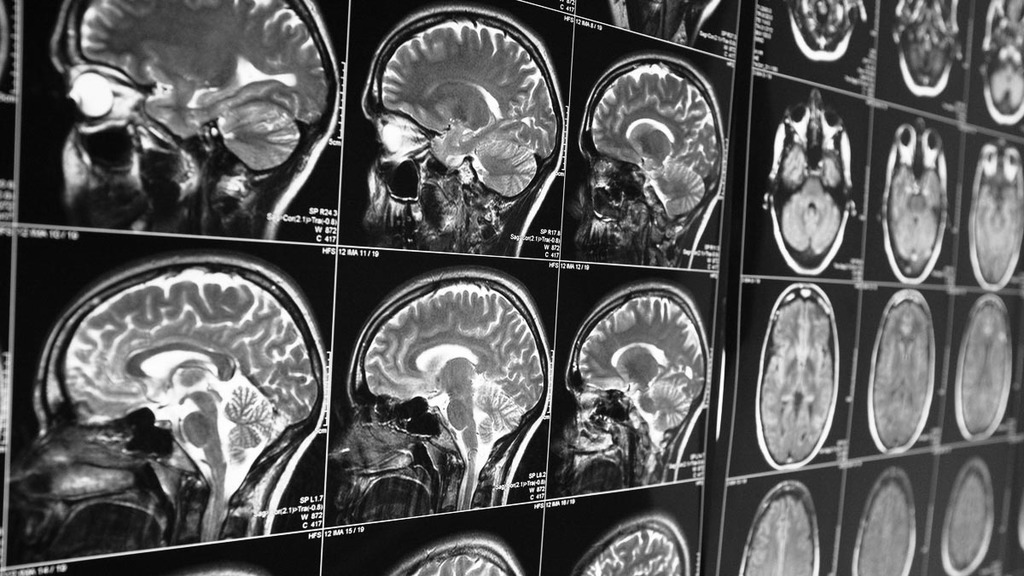

По данным Центров по контролю и профилактике заболеваний, болезнью Альцгеймера страдают примерно 5,8 миллиона американцев. Прогрессирующее заболевание является наиболее распространенной формой деменции и связано с потерей памяти и снижением когнитивных функций в областях мозга, отвечающих за мышление, память и речь.

Считается, что заболевание вызвано аномальным накоплением белков внутри и вокруг клеток головного мозга.